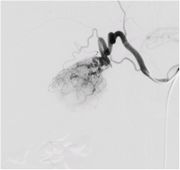

血管造影画像